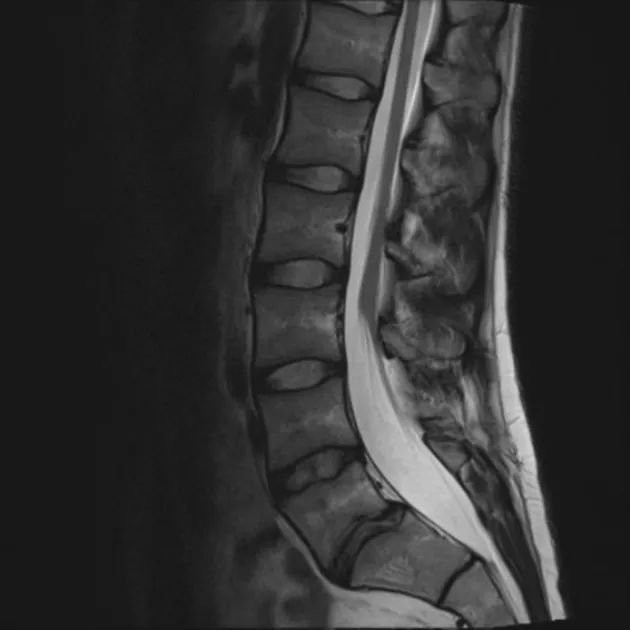

MRI可见脊髓圆锥低位,终池增宽,终丝增粗

脊髓是长圆柱形神经组织,自颈以下逐渐变细,在颈和腰部两处膨大,下端尖削为脊髓圆锥 呈圆柱状,终于第1腰椎下缘。正常情况下,胎儿在3个月时脊髓与椎管等长,以后椎管生长较快,新生儿脊髓终止于第3腰椎下缘,成人则在腰1~2椎体之间。由于不等速度生长,腰骶神经根需斜行才能达到相应的椎孔内,长的下行神经根形成马尾,且随着脊椎的弯曲,脊髓圆锥的位置可以在一定范围内上下移位,马尾及终丝则不和硬脊膜粘连。当上述发育过程发生障碍时则可导致脊髓圆锥下移及马尾神经丛和椎管后壁的粘连牵拉,使脊髓圆锥位置下降及神经终丝相对固定。